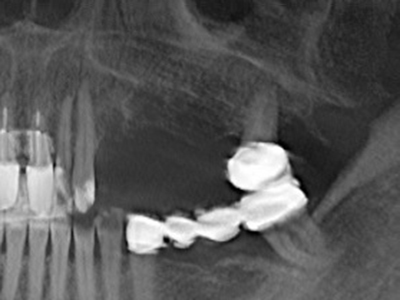

Abb. 11: Das postoperative OPTG veranschaulicht die vertikale Augmentation und Sinusbodenelevation.

Abb. 15: Die röntgenologische Ein-Jahres-Kontrolle zeigt stabile Verhältnisse des Knochenniveaus.

Abb. 17a: CT-Aufnahme eines wachstumsprogredienten Osteoms in unmittelbarer ...

Abb. 17b: Lagebeziehung zum Alveolarkanal mit Nervirritation (laterale und koronare Ansicht).